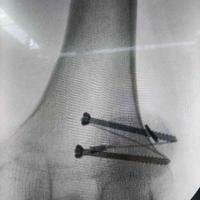

髌骨,空心钉,钛缆

查看图片需登陆

髌骨,空心钉,钛缆...

由 medjpg 发表于 2026-03-24 22:32